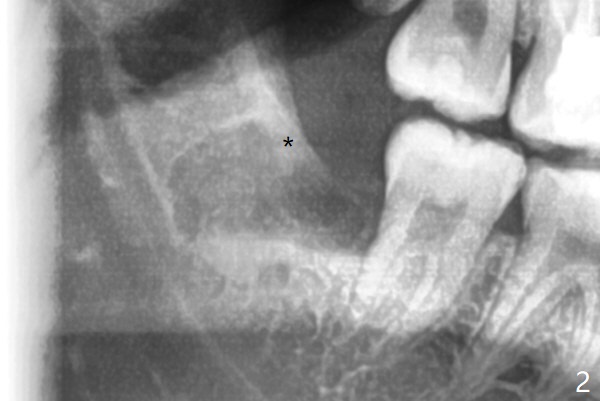

20岁女由于右下智齿疼痛就诊,诊断后,要求先拔除两个下颌智齿。外斜嵴好像跨越牙槽窝远中(图一:*),拔除似乎没有缩短外斜嵴长度(图二:*),牙槽窝放置胶原塞。